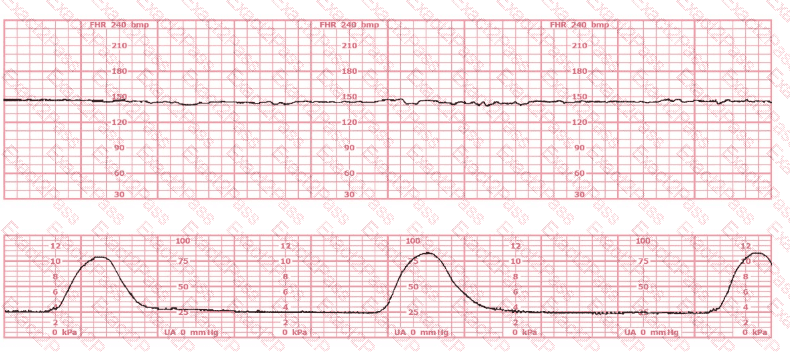

The most probable underlying fetal physiologic cause for this tracing would be:

The tracing shown is from a woman at 28-weeks gestation in the post-anesthesia care unit (PACU) after an appendectomy. She is alert and awake. Based on this fetal heart rate pattern, the most appropriate intervention is:

What is the appropriate interpretation of this tracing?